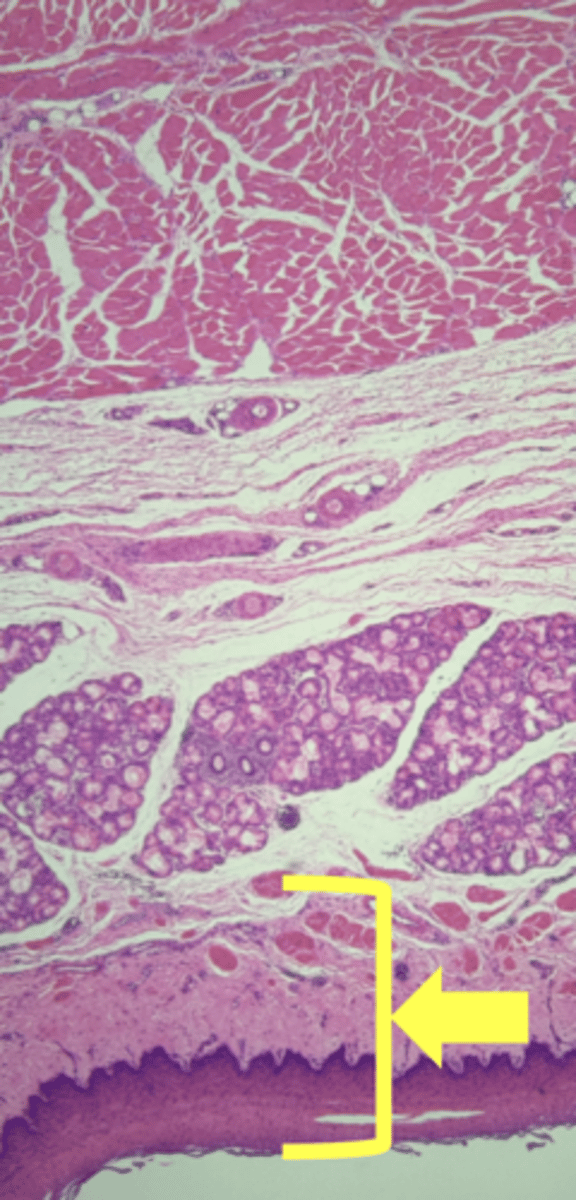

Esophagus

name the tissue

Mucosa

(esophagus)

Submucosa

muscularis externa

stratified squamous epithilium (KEY CHARACTERISTIC)

lamina propria

muscularis mucosae

circular layer

longitudinal layer